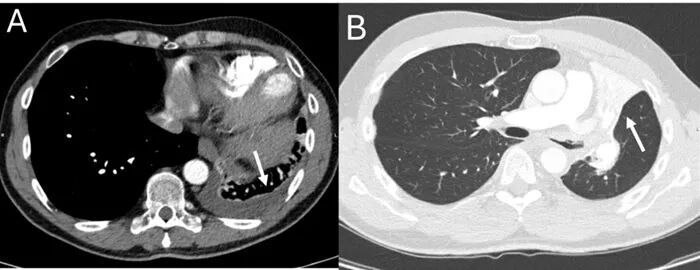

胸部 CT 扫描显示,由于左上叶支气管阻塞,左上叶和左舌叶出现广泛性肺不张(图1B)。胸突下淋巴结肿大,左侧下叶胸腔积液(图1A),疑似恶性肿瘤。

(图1 胸部CT检查)